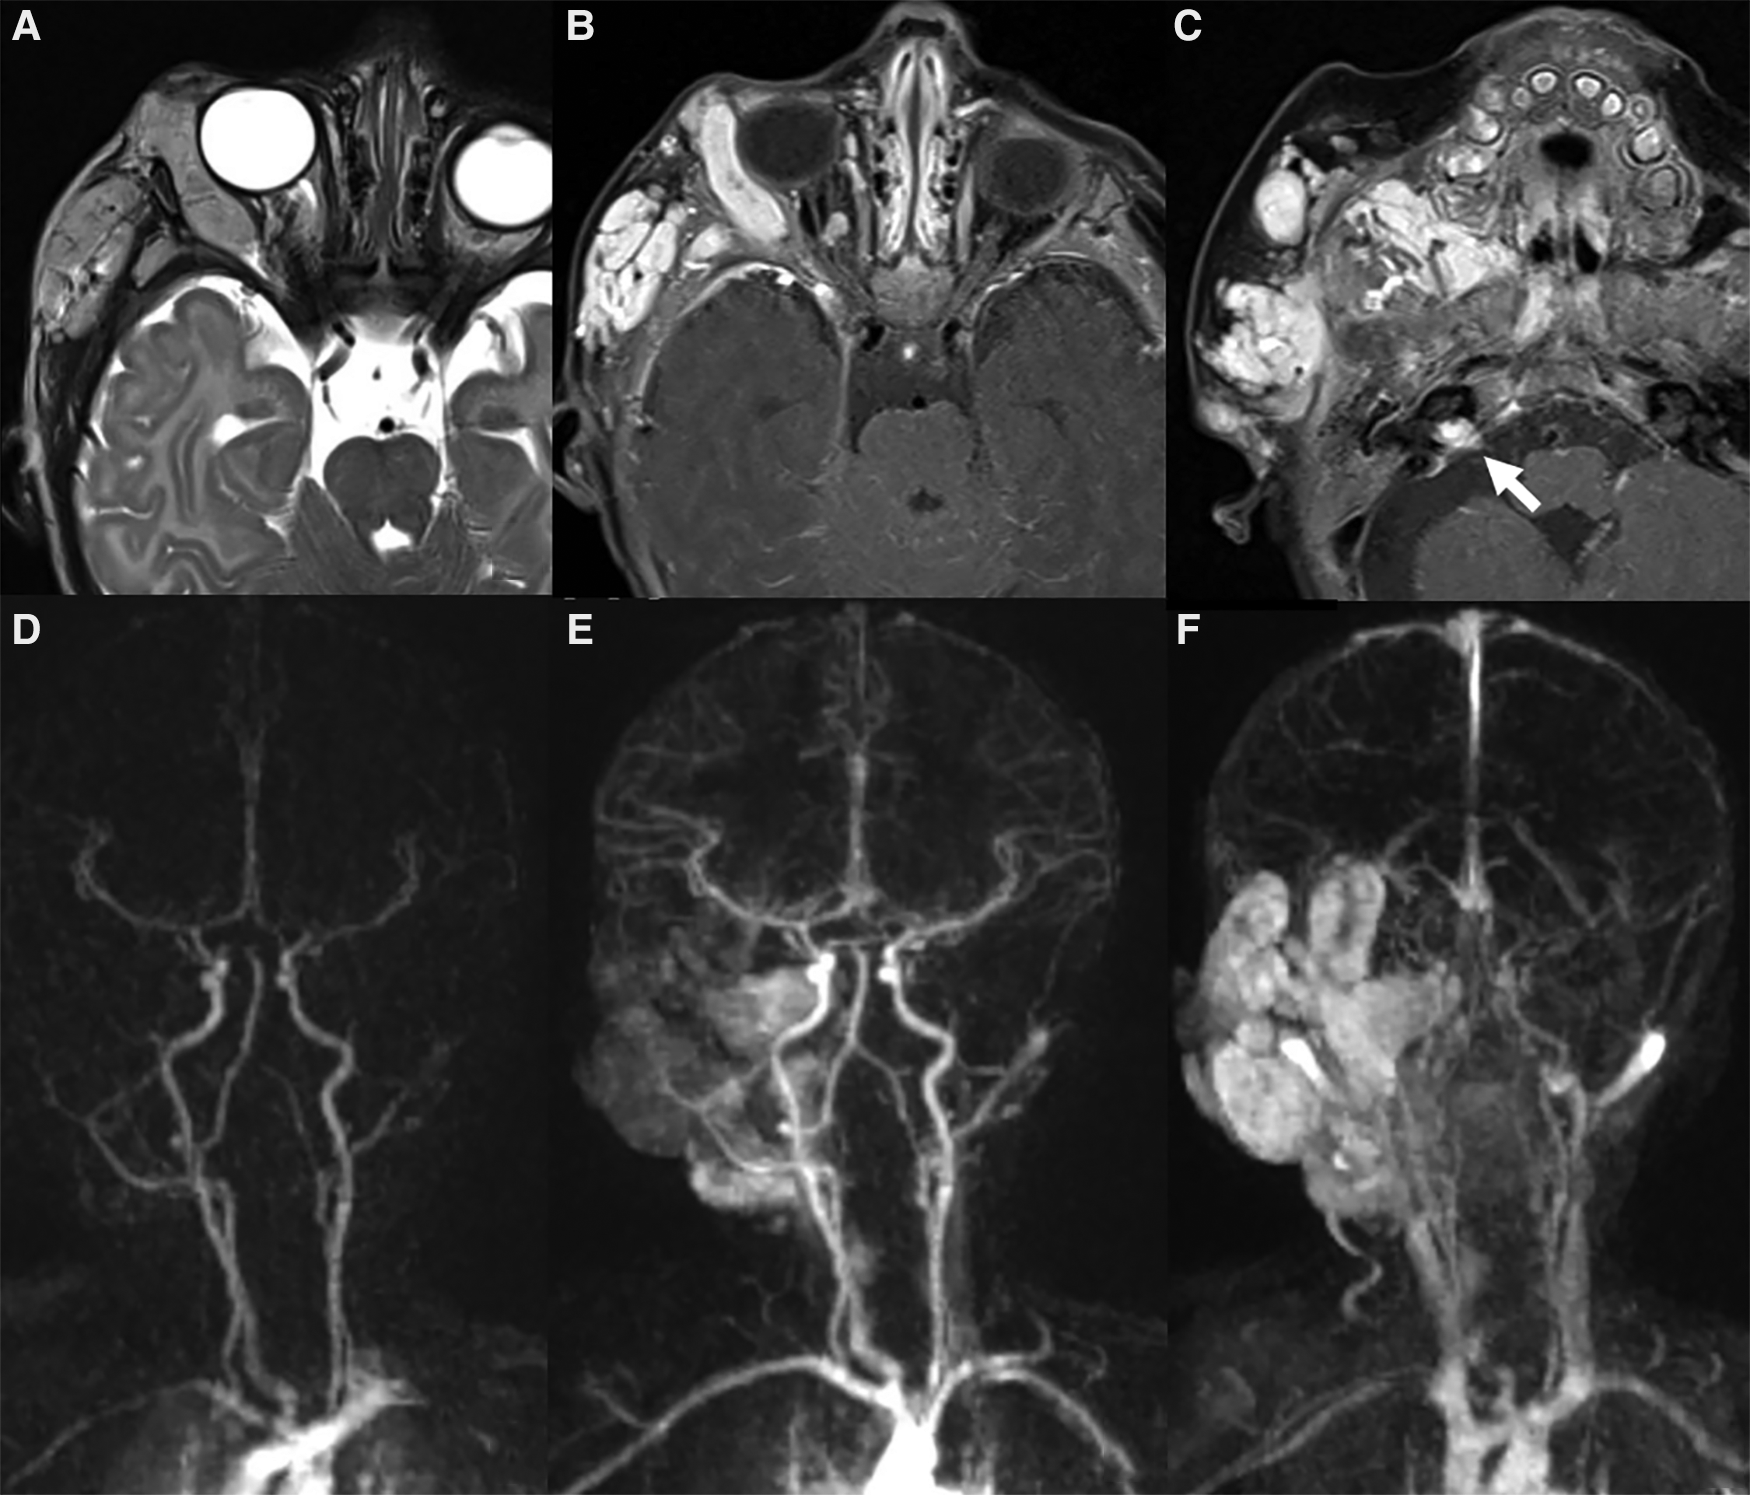

Noninvasive imaging is mandatory: it allows proper confirmation of diagnosis, sets a baseline for the patient and helps define the architecture of the malformation (68). The AVM has no parenchymal component and therefore it appears on gray-scale US as a poorly defined heterogeneous structure, usually surrounded by fat. At the color Doppler examination, the malformation is a high flow lesion: there are numerous vessels (“high vascular density”) with increased diastolic flow and arterialization of the draining vein. The spectral Doppler analysis shows arterial vessels with high-velocity flow and low resistive index (64). MRI and CT angiography are ideal noninvasive modalities for visualizing the entire course and extent of an AVM, to assess organ involvement and for planning endovascular or surgical management (13). MRI is the finest technique to estimate the expansion of the malformation and its rapports with adjacent structures (69). Dilated and tortuous vascular structures representing the hypertrophied feeding arteries and the draining veins are seen, appearing as prominent flow voids on spin-echo sequences, in the absence of a discrete enhancing soft tissue mass, thus aiding in the differential diagnosis with hemangiomas (Figure 11). In the very early cases, subtly hypertrophied vessels can be the only findings visible (Figure 11). In case of hemorrhage or thrombosis, foci of hypersignal on T1w images will be found (Figure 12). When small, the AVM usually involves a single compartment whereas in larger lesions or those that have been previously treated the nidus may be difficult to define as pronounced secondarily induced angiogenesis is present (56) or may be centered in more than one compartment. At MRA there is rapid enhancement of the tangle of vessels, with early enhancement of the draining veins (Figure 12). Intraosseous infiltration causes low marrow signal intensity on T1-weighted images (70). The introduction of time-resolved MRI sequences allowed to evaluate the hemodynamics of an AVM, giving the precise topography, mapped in time, of arterial feeders and venous drainage prior to DSA: the progressive opacification of the nidus and of the draining veins can be well-demonstrated and critical findings such as arterial or intranidal aneurysms or venous varices can be easily visualized (Figures 11, 12). In children, the identification or documentation of an AVM in the cerebro-facial region should prompt investigation for other clinically silent AVMs along the same metameric level due to possible syndromic associations (71). In case of suspected bone involvement or when the AVM is centered within the bone, CT and CTA may be the best imaging tools. Intraosseous AVMs present as osteolytic lesions with intense enhancement, as the lytic bony defects represent dilated intraosseous venous pouches or dilated draining veins (56). CT may also show complications such as bone thickening (or mature periosteal reaction), seen as a result of chronic venous hypertension, or osteolysis. DSA remains the most invaluable tool to confirm the diagnosis: it delineates the angioarchitecture and real-time hemodynamics of the AVMs with no venous contamination of the arterial phase, allowing also their endovascular treatment when necessary (Figures 11, 12).

Figure 11. Mr and DSA of a 2-year-old boy referred for follow-up of an orbital “hemangioma” treated with propranolol and worsening of proptosis. Axial T2 TSE sequence (A) shows markedly dilated and tortuous vessels (arrowheads) in the extra- and intra-conal compartments of the right orbit without a discrete parenchymatous component, raising the suspicion of an AVM. MR angiography revealed a tangle of vessels with a small nidus and early venous drainage (B). The findings were subsequently confirmed at DSA (C).

Figure 12. Right orbital AVM in a 14-year-old girl with progressive proptosis, strabismus and visual loss. A red pulsatile mass in the upper lid was already evident at clinical examination (A); a thrill was also perceptible at palpation. Coronal T2 TSE sequence (B) shows a massive trans-spatial expansile lesion occupying the entire orbit, distorting its anatomy; signal intensity is highly inhomogeneous due to the presence of tortuous flow-voids (black arrow in B) and blood products of varying age (white arrow in B). The other MR sequences did not demonstrate any intracranial extension of the vascular malformation (not shown). The arterial phase of the DSA (lateral view, C) depicts the dilated and slightly tortuous right ophthalmic artery (grey arrowhead, arising from the supraclinoid segment of the internal carotid artery) feeding the orbital AVM, the nidus (white asterisk) and the early opacification of the draining vein, the superior ophthalmic vein (white arrowhead). The venous drainage is better seen in the venous phase of the DSA (lateral view, D), occurring mainly through the dilated right superior ophthalmic vein (white arrowhead), which drains into the cavernous sinus.